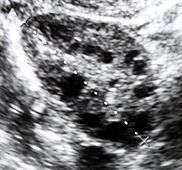

Ultrasound of a polycystic ovary

Polycystic ovary syndrome (PCOS) is an endocrine disorder characterized by an excess of androgens produced by the ovaries. It is estimated that approximately 90 percent of women with PCOS demonstrate hypersecretion of these hormones.[6] A concrete cause for this condition is currently unknown. Speculations include genetic predisposition, although the gene or genes in particular have yet to be identified.[7] Evidence suggests that the condition may have a hereditary basis. Other possible causes include the effects from an increase in insulin production. Insulin itself has been observed capable of inducing excess testosterone levels in the ovaries.[8] Elevated insulin concentration in the body leads to lower production of sex hormone binding globulin (SHBG), a regulatory glycoprotein that suppresses the function of androgens.[9] High blood levels of insulin also work in conjunction with ovarian sensitivity to insulin to cause hyperandrogenemia, the primary symptom of PCOS. Obese individuals may be more biologically inclined to display PCOS due to markedly higher amounts of insulin in their bodies. This hormonal imbalance can lead to chronic anovulation, in which the ovaries experiences difficulty releasing mature eggs. These cases of ovulatory dysfunction are linked to infertility and menstrual disturbances.[6][10]